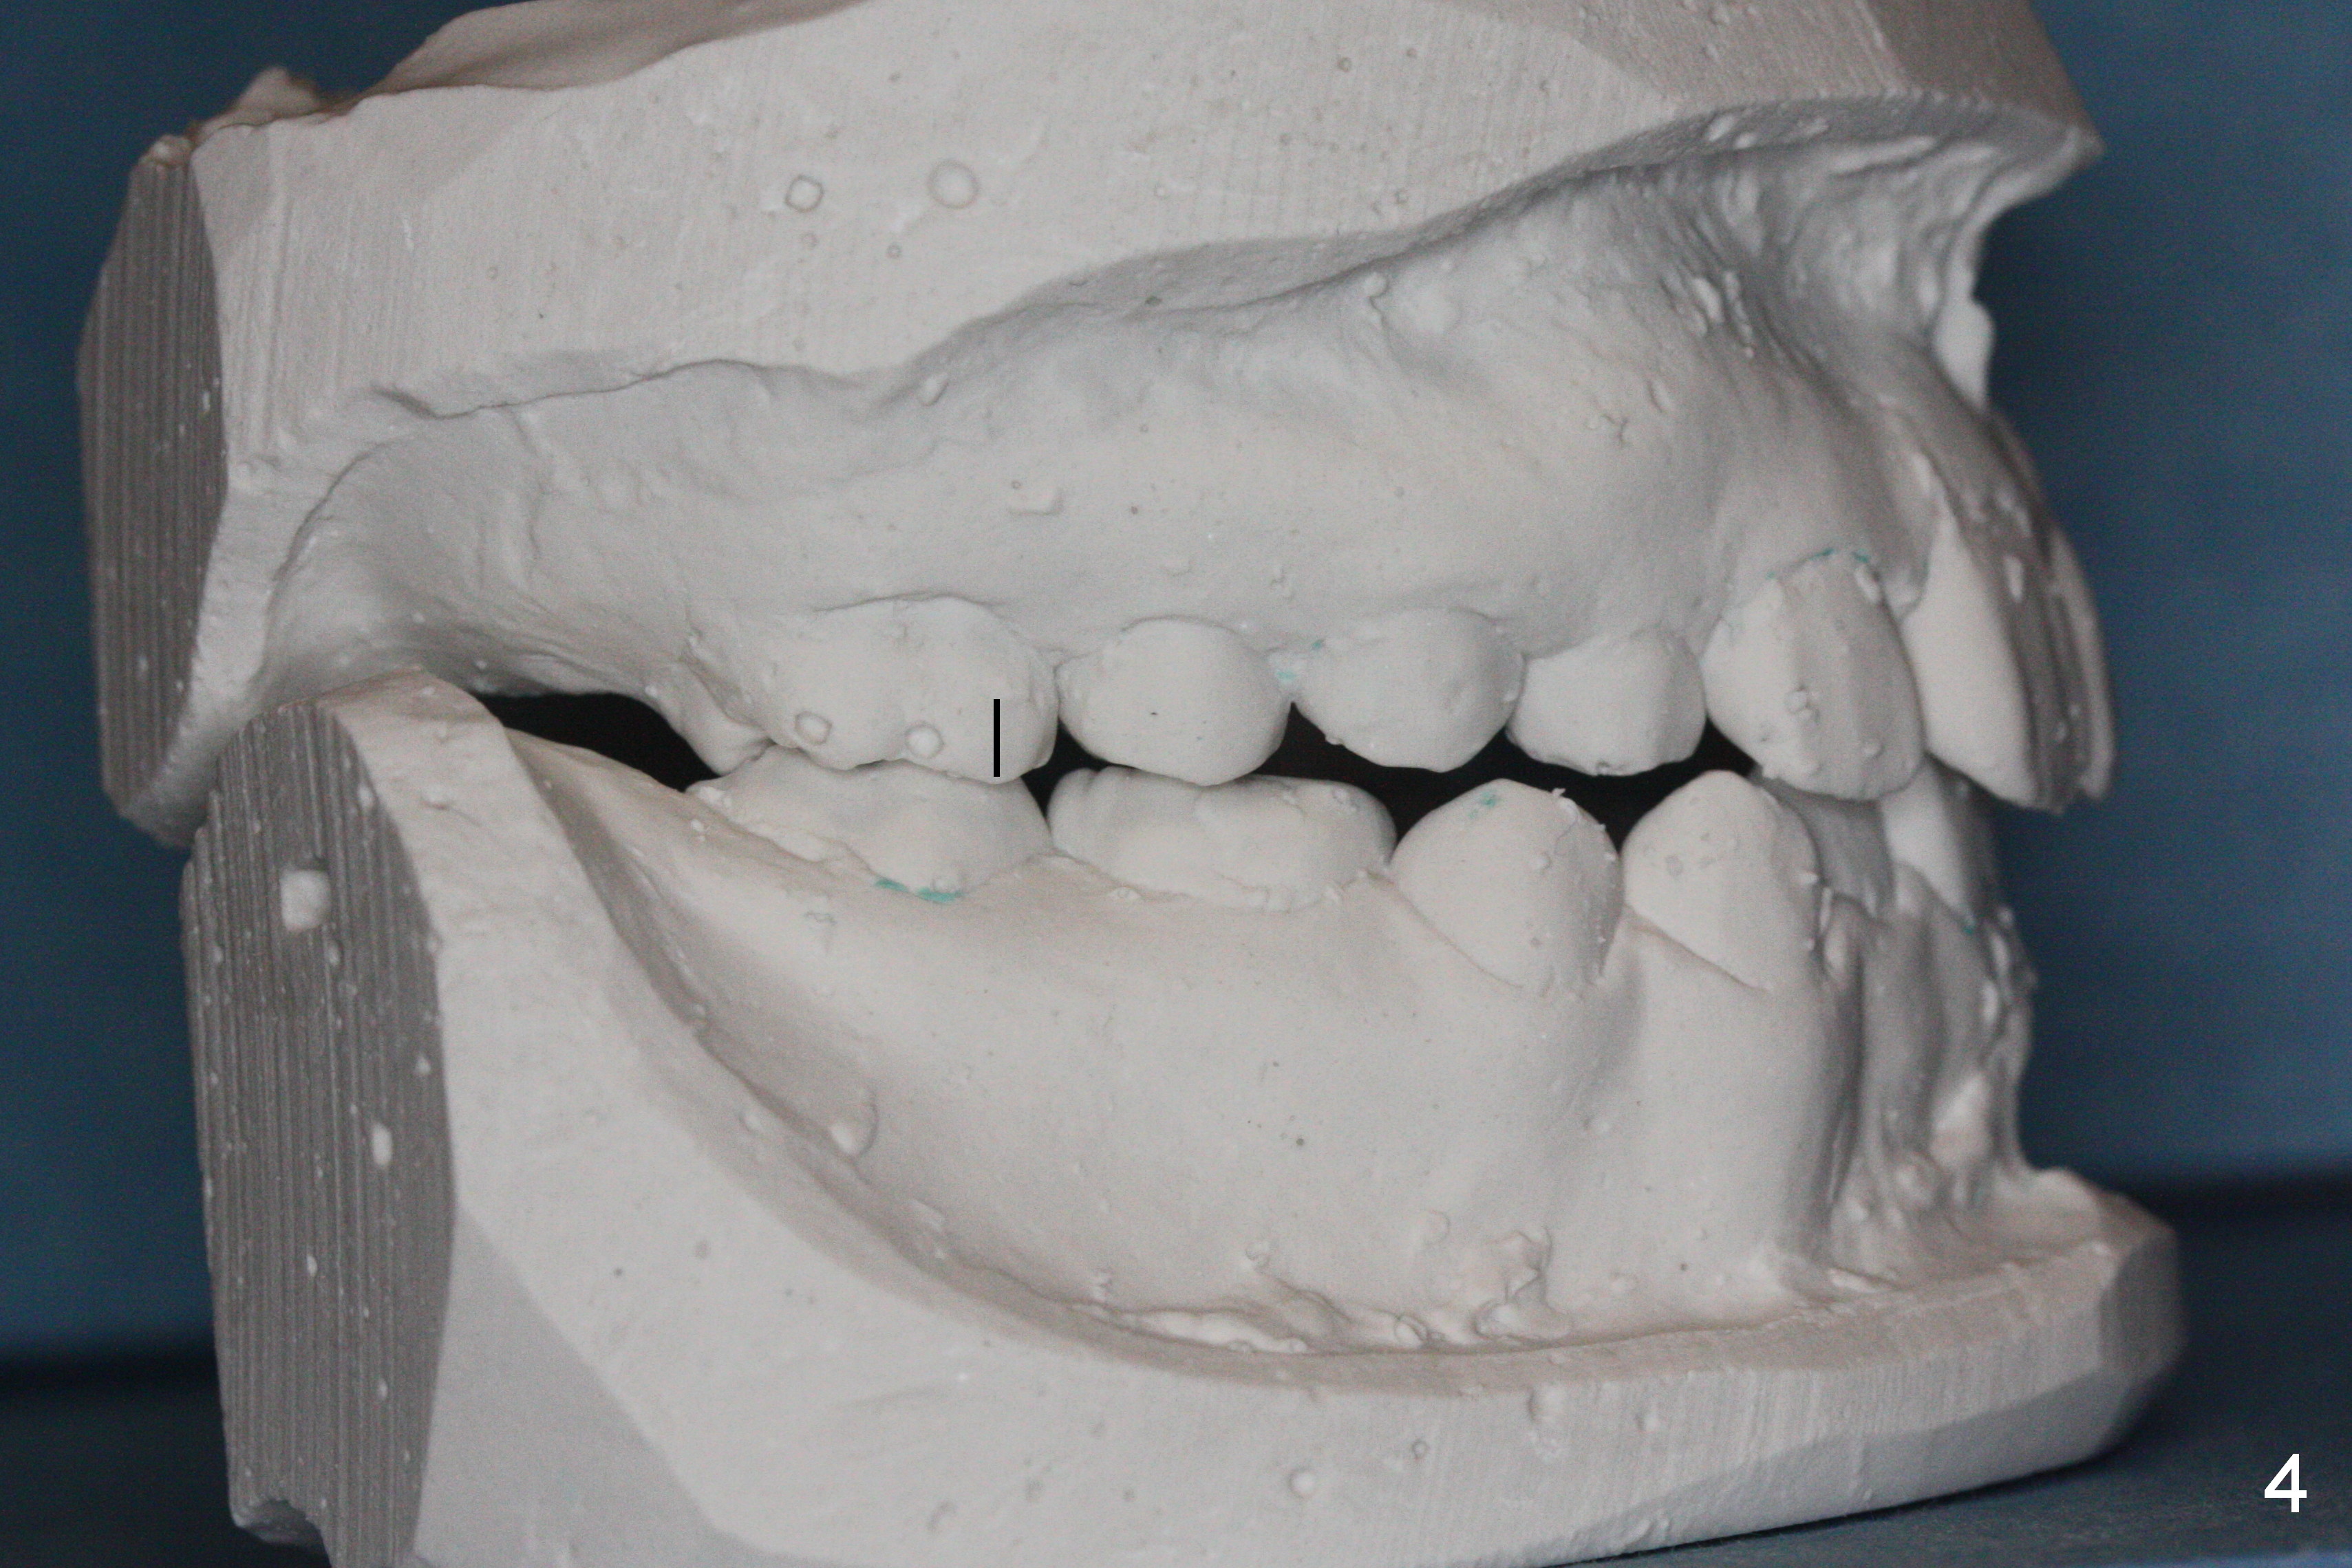

While the upper right bicuspids have erupted, the upper left ones are unerupted and blocked (Fig.2, 6). It appears that the tooth #14 has been mesially shifted (compare Fig.4,5). A space regainer is fabricated (Fig.9). It is not completely seated when cemented, especially at H. The wire holding open coil spring fractures next day. It appears that H is not a good anchor with mobility II. It should be extracted. The mesial anchor will be the tooth #10. If there is sign of anterior tooth protrusion after regainer activation, a mini implant (Tomas, Fig.10 red circle) should be placed in the anterior palate parasagitally and bonded to the cross palatal wire (^).

Nearly 2 months post regainer placement, UL6 appears to have been distalized (Fig.11 arrow), but UL4,5 have not erupted (Fig.12), while UL1,2 are displaced (Fig.13). Diode laser is used to expose the tooth buds, which are deeply seated (Fig.14). If they do not erupt soon, a mini implant should be placed for anchorage (Fig.10). Use several power chains to retract the anterior arm, while drill through the Nance appliance (high speed handpiece) for mini implant placement.